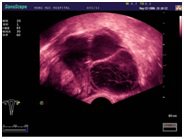

На сегодняшний день УЗИ аппараты в Медицинском центре «АКВА МЕД МАРИН» оснащены многофункциональными датчиками, что дает возможность проводить исследования широкого спектра.

В Медицинском центре «АКВА МЕД МАРИН» при помощи профессиональной аппаратуры, проводится: